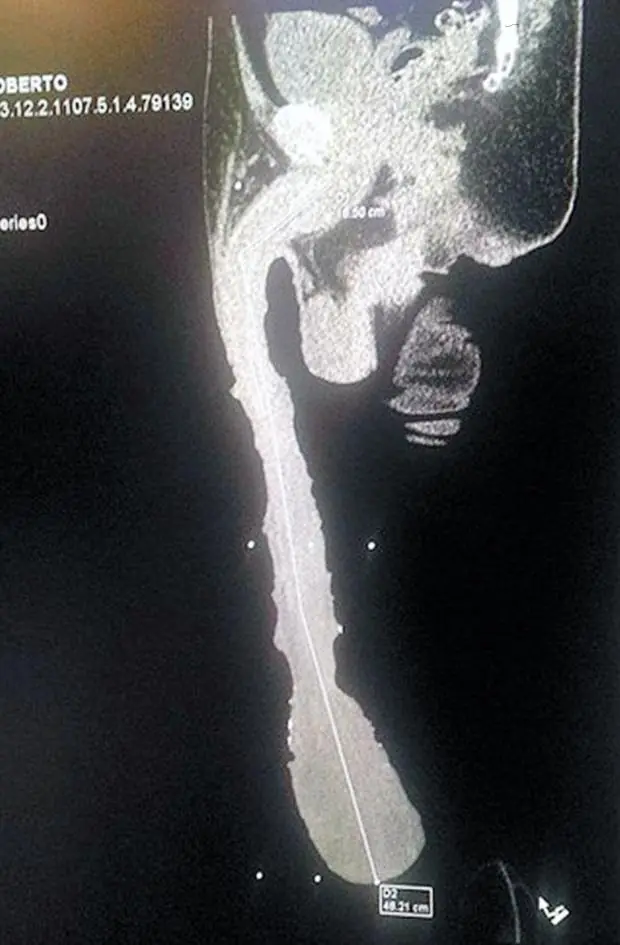

Los profesionales contaron al diario La Vanguardia que “de acuerdo con la tomografía en tercera dimensión sí es su cuerpo; se descarta una prótesis y sabemos que el cuerpo principal mide unos 16 centímetros y el resto, para llegar a 48.2, es un exceso extraordinario de piel. Sólo un urólogo y seguramente otros exámenes podrán determinar al 100 por ciento”.